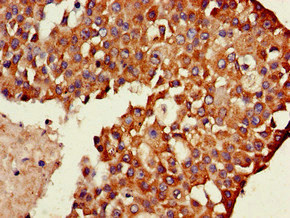

Immunohistochemistry of paraffin-embedded human breast cancer using CSB-PA025362LA01HU at dilution of 1:100